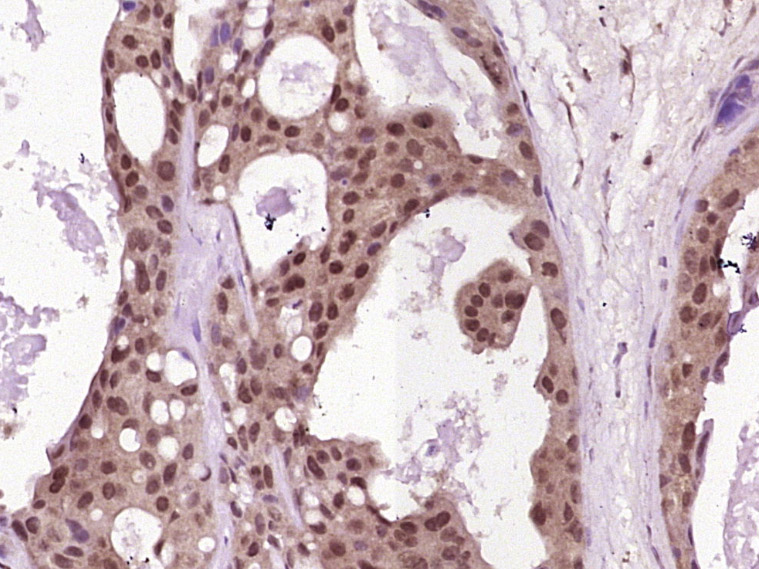

Paraformaldehyde-fixed, paraffin embedded (human breast carcinoma); Antigen retrieval by boiling in sodium citrate buffer (pH6.0) for 15min; Block endogenous peroxidase by 3% hydrogen peroxide for 20 minutes; Blocking buffer (normal goat serum) at 37°C for 30min; Antibody incubation with (MLH1) Polyclonal Antibody, Unconjugated (bs-23633R) at 1:400 overnight at 4°C, followed by operating according to SP Kit(Rabbit) (sp-0023) instructionsand DAB staining.